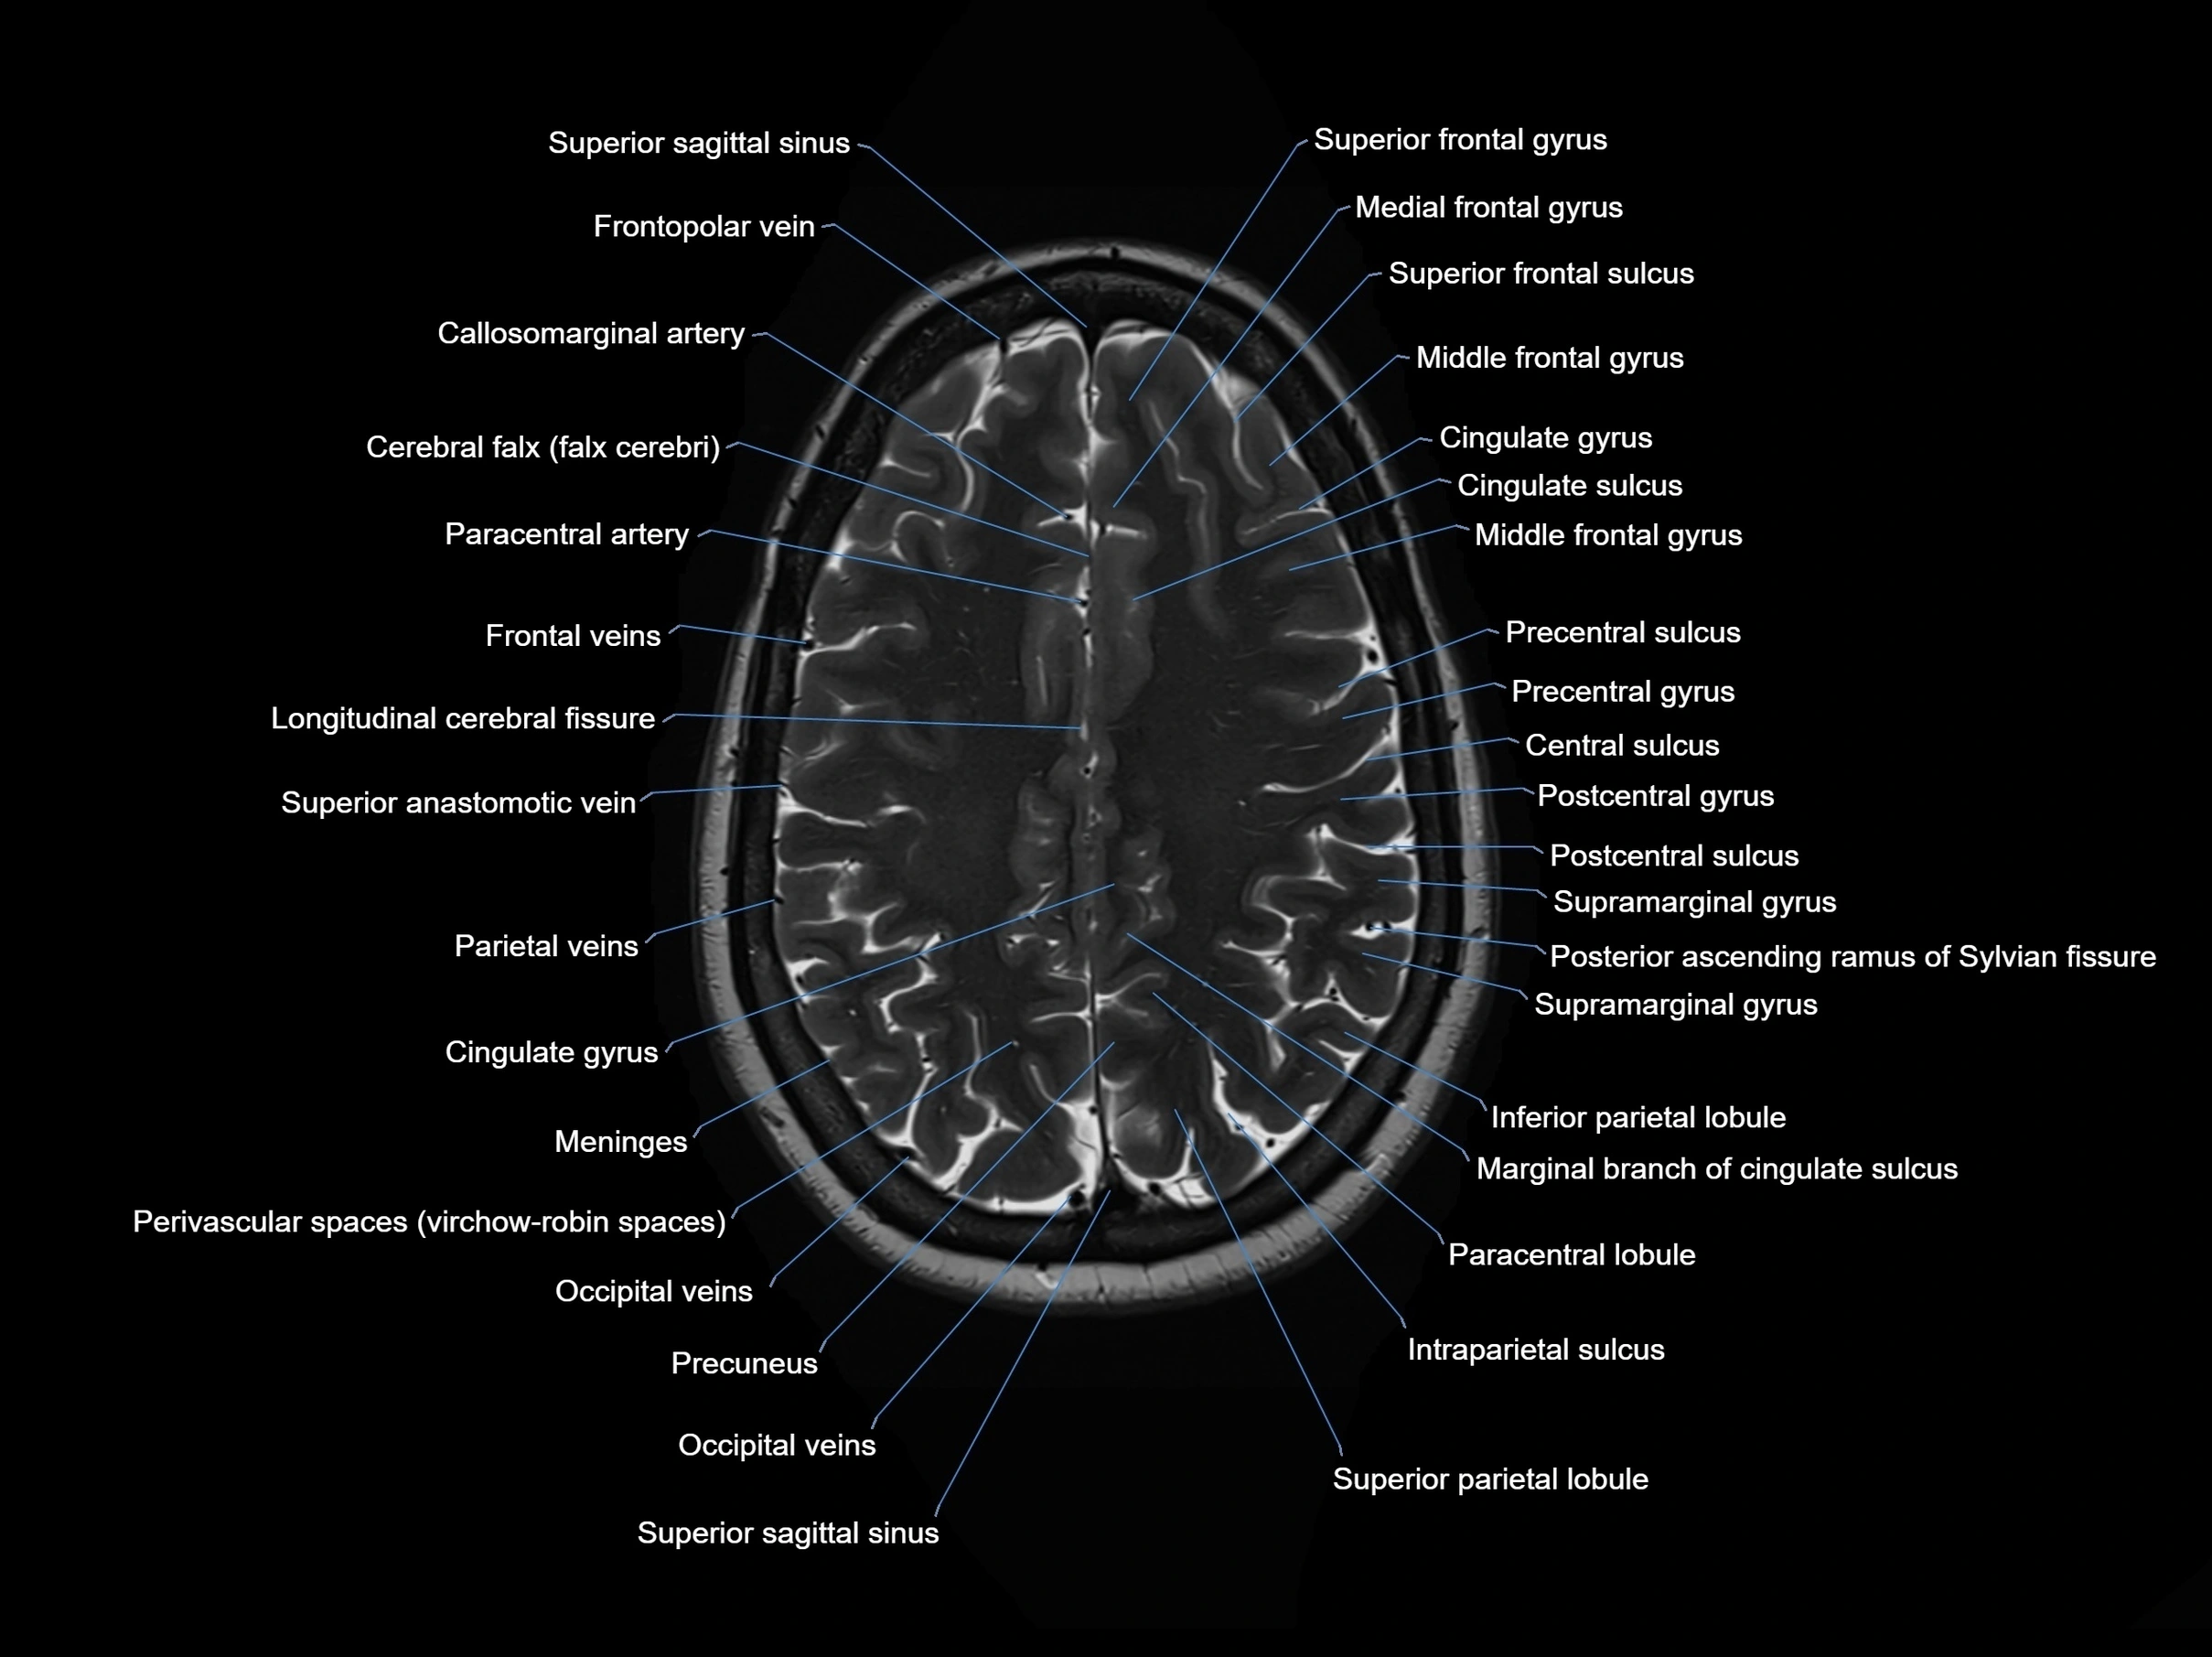

MRI images